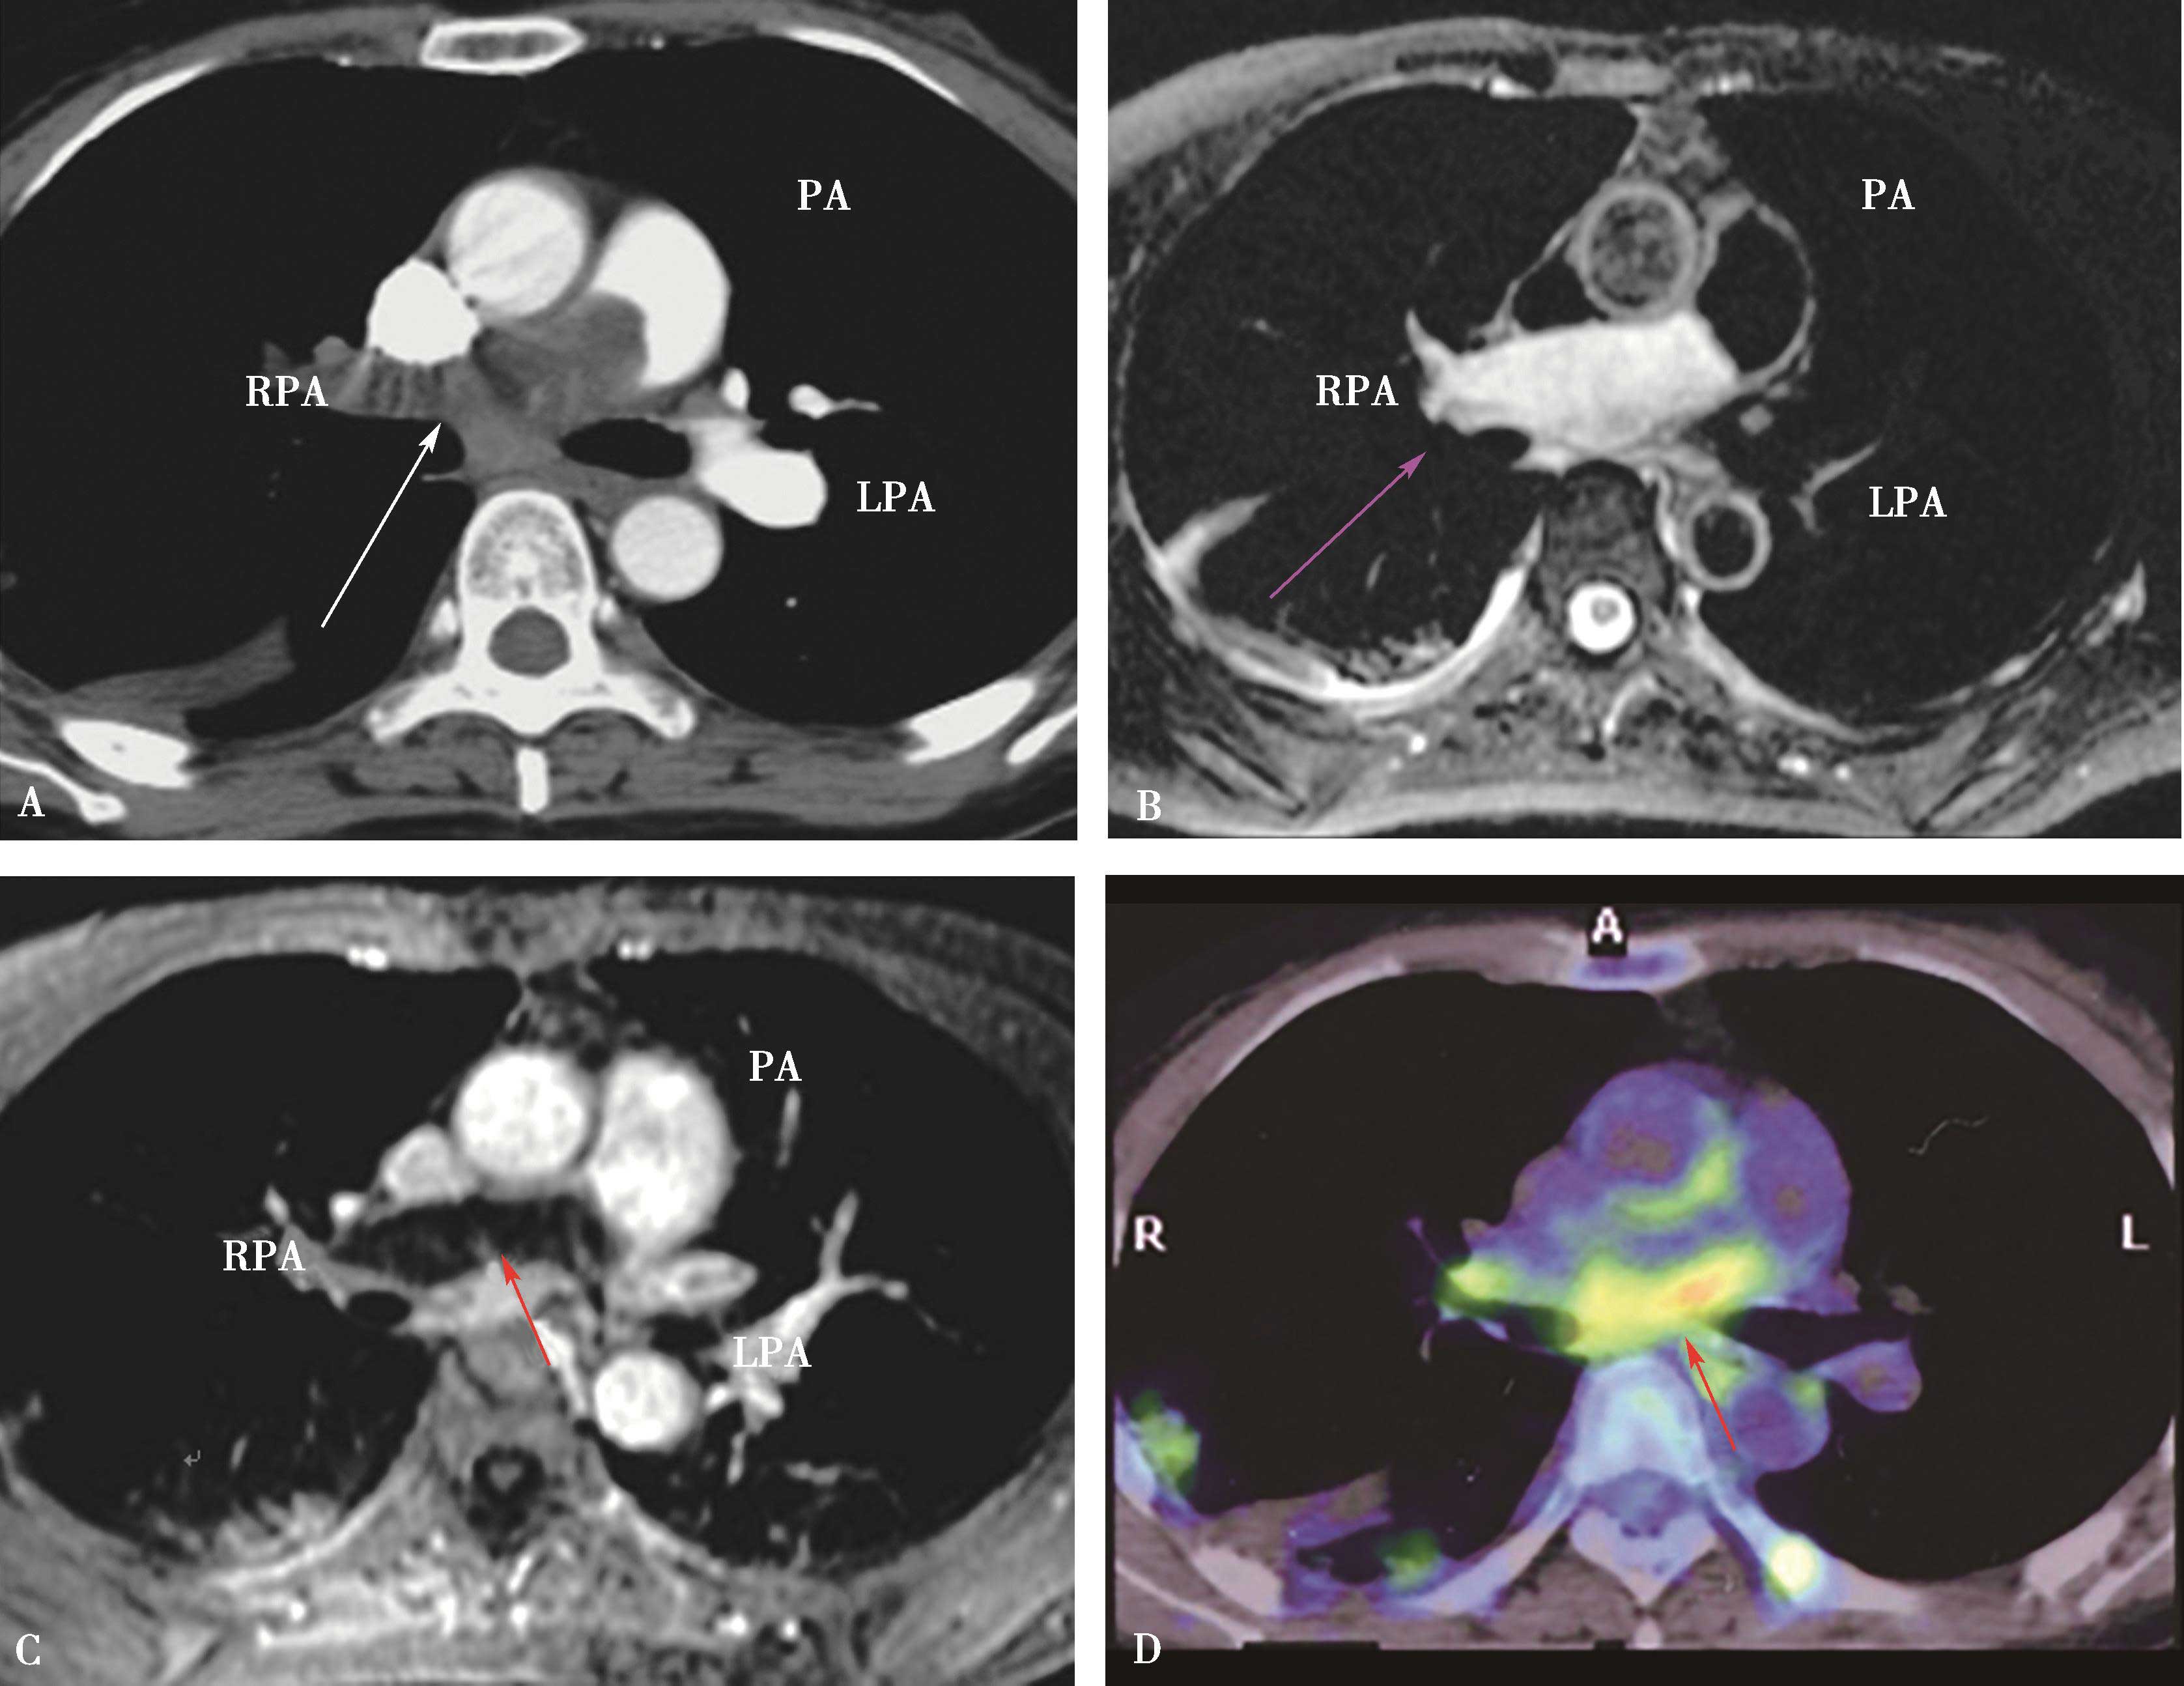

图8-3-2 正常肺组织

A.双能CT肺灌注成像(DELPI);B.核素 99m Tc-MAA SPECT/CT

图8-3-3 男,73岁,右肺下叶肺栓塞

A.双能CT肺灌注成像(DELPI);B.核素 99m Tc-MAA SPECT/CT。CT灌注扫描与核素检查结果一致

图8-3-4 男,69岁,双肺多发、急性肺栓塞

A.双能CT肺灌注成像(DELPI);B.核素 99m Tc-MAA SPECT/CT,CT灌注扫描与核素检查结果一致

2.CT肺灌注成像肺栓塞的诊断应用 CTPA及肺部灌注成像可以显示肺动脉管腔形态,可以显示肺栓塞所引起的肺动脉形态学变化,同时提供栓塞后肺组织微循环改变,并以灌注伪彩图的形式直观地显示栓塞引起的灌注缺损区,为诊断及治疗提供更多信息,指导治疗,评价治疗效果。但CT肺灌注成像不能直接显示栓子的部位和大小,诊断应该结合CTPA所显示的肺动脉狭窄及梗阻,做出诊断。但是,研究表明灌注扫描对检出亚分段的栓塞,可以提高CTPA诊断敏感性(20%),有重要价值。与核素对照研究,高度相关( r =0.884)(图8-3-2~图8-3-6)。